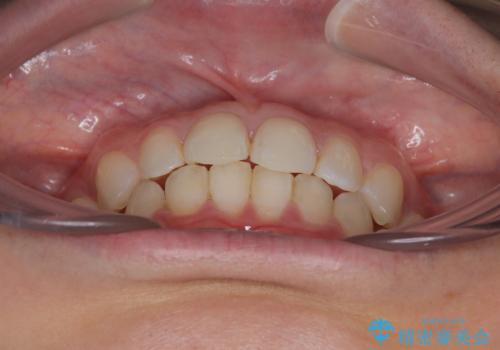

- 前歯のデコボコと歯肉に埋もれている奥歯を気にして来院された患者様です。

インビザラインでの治療を希望されていましたが、左右の下顎大臼歯が歯肉に埋もれており、特に右側は歯軸が顕著に傾斜していたため、インビザライン単独での治療は困難と判断し、ワイヤー装置を併用することとしました。

ワイヤー装置での下顎臼歯改善には時間がかかることが予想されたため、下顎のワイヤー矯正と並行して上顎をインビザラインで整え、その後インビザラインにより上下歯列を整える矯正治療を行うこととしました。